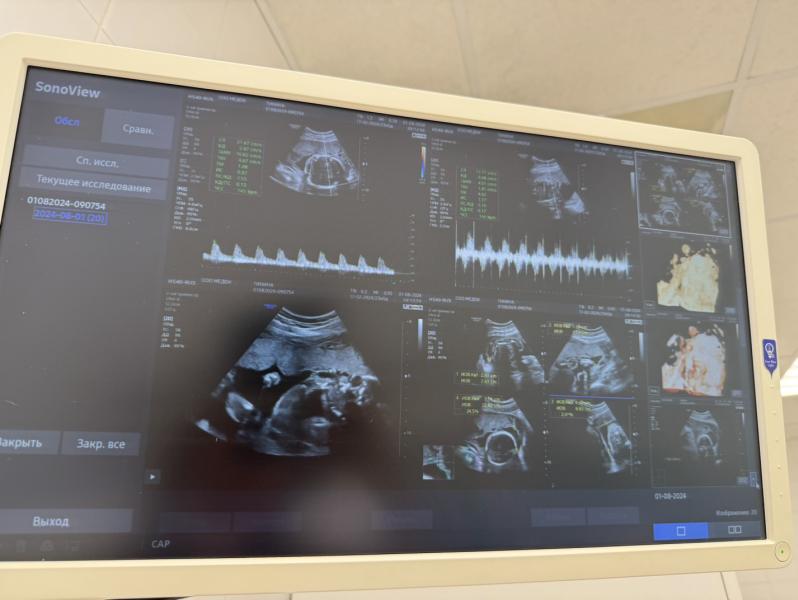

Как летит время 😱 Уже 23 недели 5 дней, растет принцесса 👸🏼, вес 576 грамм

Вчера ходила на первый допплер в любимый Медок, с кровотоками все в порядке, заодно и быстро посмотрели малышку.

Я стала жаловаться врачу, что не так активно чувствую шевеления, только под вечер прыгает) А она оказывается такая аккуратная девчуля, лежит спокойно, ножками и ручками шевелит, пальчик сосет 😃

У меня еще плацента по передней стенке, поэтому защищает меня от небольших пиночков, чувствую только, когда прям сильно. Но врач сказала, что скоро вес наберёт и покажет еще))) ❤️🎁